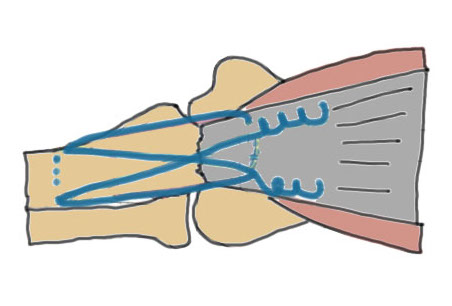

Tension suture fixation

Indication

Type 2A fractures

Fracture proximal to center of rotation / midpoint of trochlea

Don't want to remove prominent wires

Technique

Drill hole in distal ulna

- pass sutures through drill hole

- pass sutures through medial and lateral limbs of the triceps insertion

Results

Phadnis et al Should Elbow 2020

- 168 olecranon fracture / osteotomy fixation

- TBW v suture fixation v olecranon plates

- re-operation rate: TBW 36%, plate 11%, suture group 2%

- suture group (n=41): 1 reoperation, 1 asymptomatic nonunion